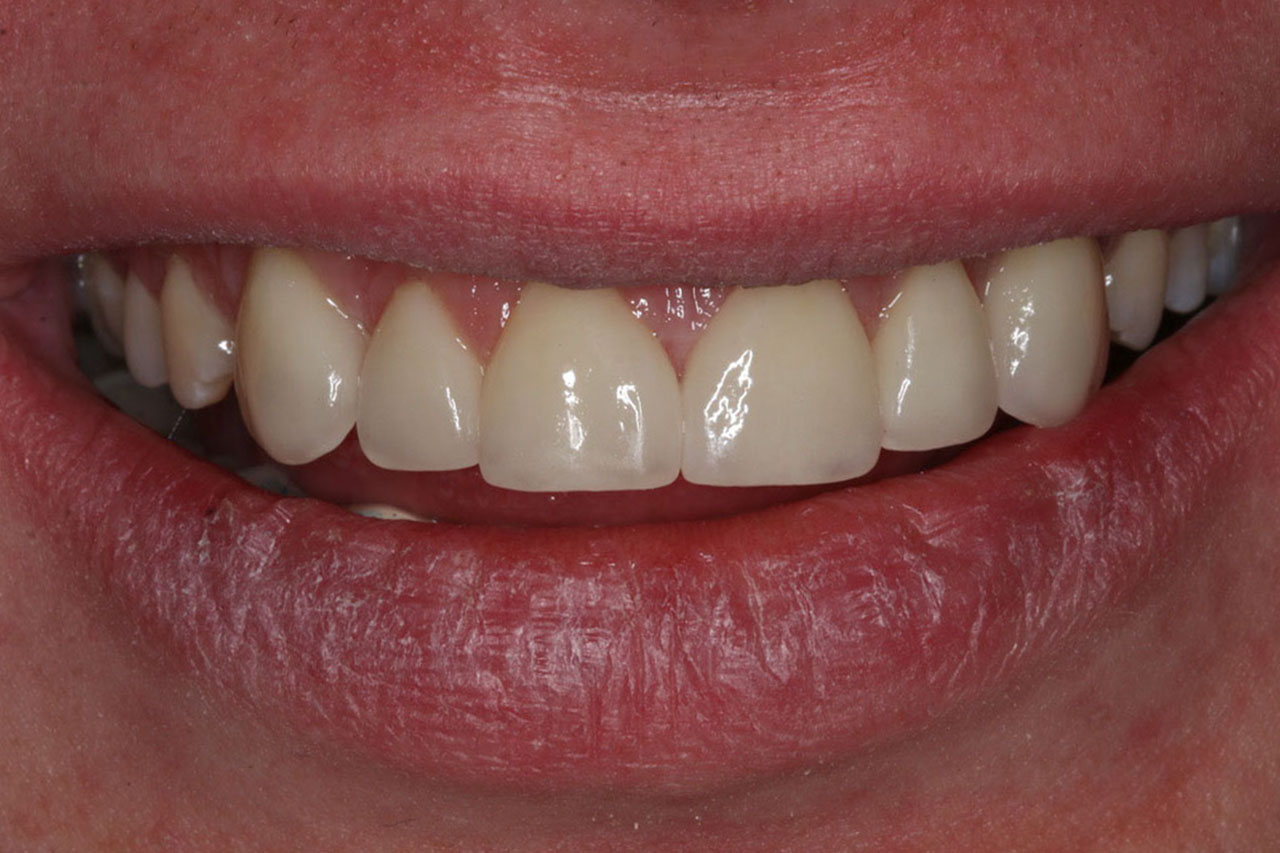

Pragniemy przedstawić Państwu metamorfozy uśmiechów, które zostały wykonane w My Clinic. W początkowej fazie leczenia fotografujemy stan uzębienia by móc go porównać po jego zakończeniu. Efekty jakie uzyskujemy są możliwe dzięki odpowiedniemu planowi leczenia, wykorzystaniu najlepszych materiały stomatologicznych oraz doświadczeniu kadry specjalistów, którzy troszczą się o uśmiechy naszych Pacjentów.

1. Korony pełnoceramiczne, nakładolicówki kompozytowe,

korony na implantach